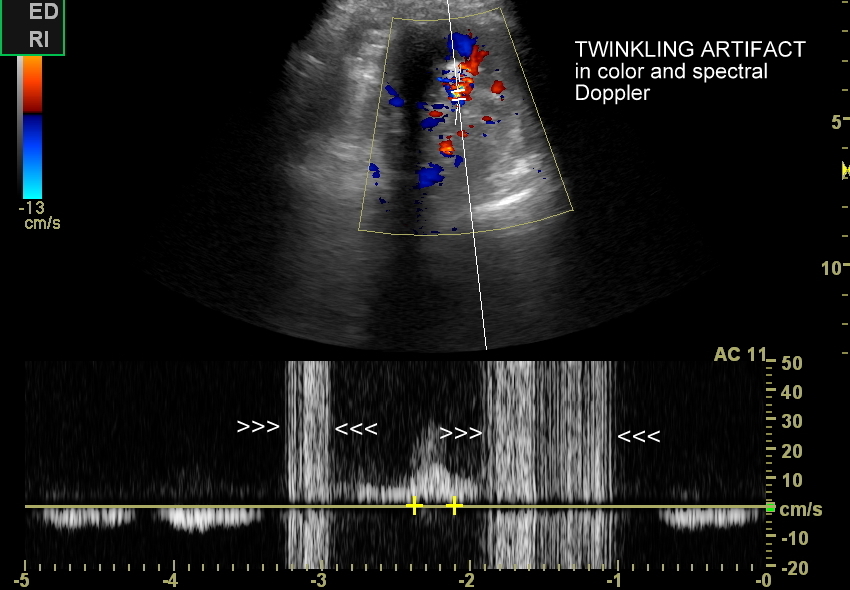

Ważnym trybem pomocniczym jest color-Doppler, w którym to trybie uzyskuje się tzw. artefakt migotania, często nawet na bardzo drobnych złogach niewidocznych w trybie B. Uzyskanie efektu migotania jest niestety zależne o jakości aparatury USG, a także od ustawień Dopplera i software’u.

W modalnościach dopplerowskich oprócz prezentacji color-Doppler artefakt migotania pojawia się także w trybie Dopplera spektralnego. Otóż po umieszczeniu bramki dopplerowskiej na złogu uzyskuje się charakterystyczny, dźwiękowy objaw trzeszczenia, a na obrazie wykresu wypełnienie sygnałem całego spektrum częstotliwości.